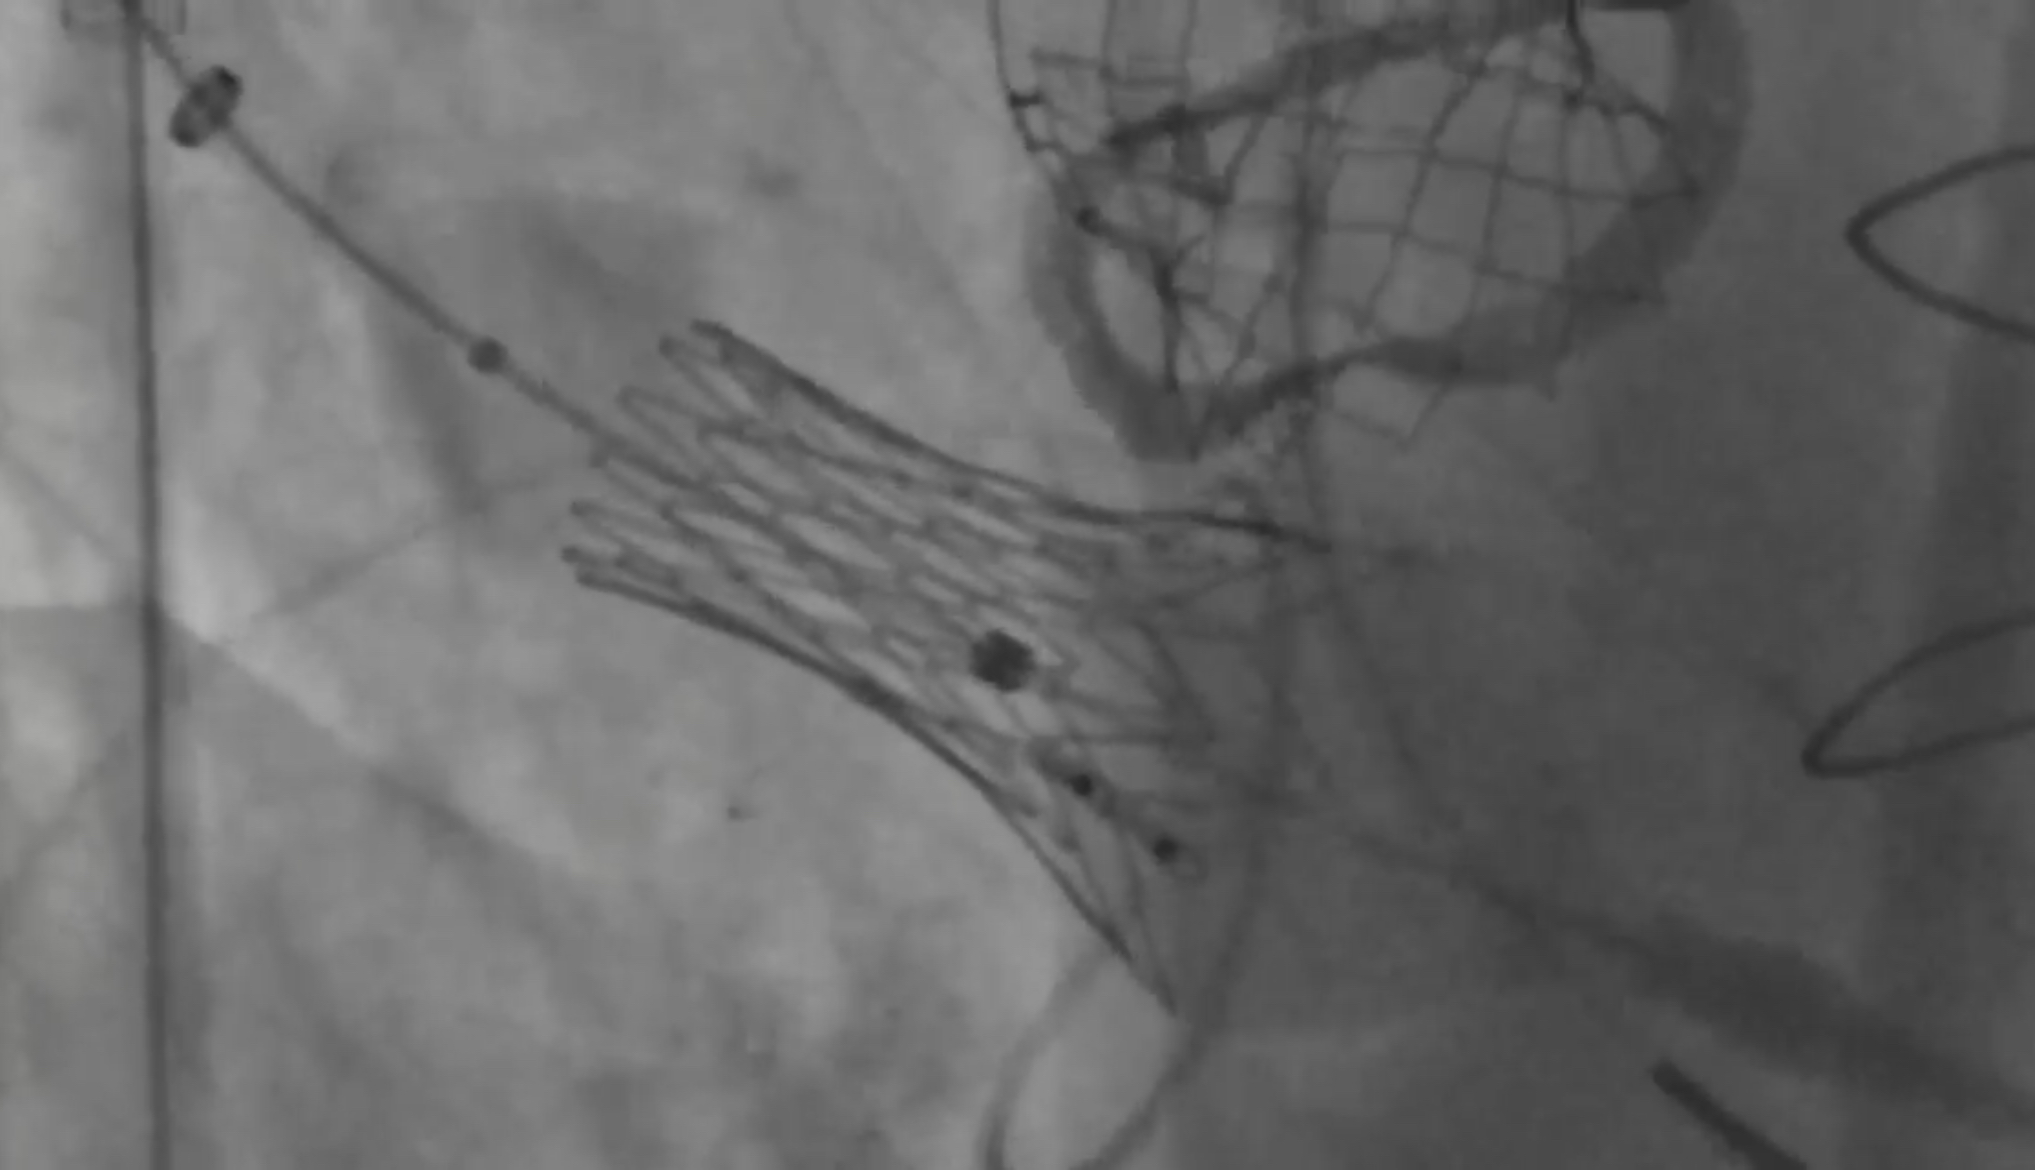

Anteris pushing boundaries…

The above image is a screenshot from an Xray Fluroscopy video of a world first Valve-in-Valve replacement of both the Aortic valve and the Mitral valve of a patient using Anteris’ DurAVR. Hopefully there is an official Anteris press release this week about this.

This is exceptional as DurAVR — as the name suggests — is designed only for Aortic Valve Replacement, but clearly has some versatility. Without the text I’ve pasted below I’d have no idea what I was looking at, but you can see the mesh frame in the top right is already expanded — that is the Aortic DurAVR from the month before. The one on the left is the Mitral DurAVR implantation during the balloon expansion. There appears to be no previous mesh frames/stents as the earlier valve replacements in this patient were surgical (as opposed to Transcatheter as in TAVR). In both cases the DurAVR is placed inside the surgically replaced valves, which themselves are inside the patient’s failed native valves. Dr Meduri is Anteris’ Chief Medical Officer.